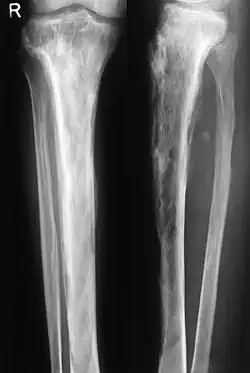

Wesentlich für die Diagnose ist das Röntgenbild, in dem schon im Frühstadium der Erkrankung die Osteolyse nachgewiesen werden kann. Der erhöhte Knochenumbau kann mittels Knochenszintigraphie nachgewiesen werden.